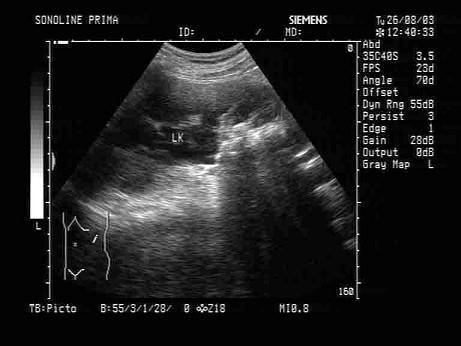

问题 某患者因左肾区疼痛、血尿就诊,根据其超声声像图,最可能的诊断为?(?)

选项 A.正常图像 B.左肾结核 C.输尿管结石 D.左肾结石 E.左肾多发性结石并肾积水

答案 E